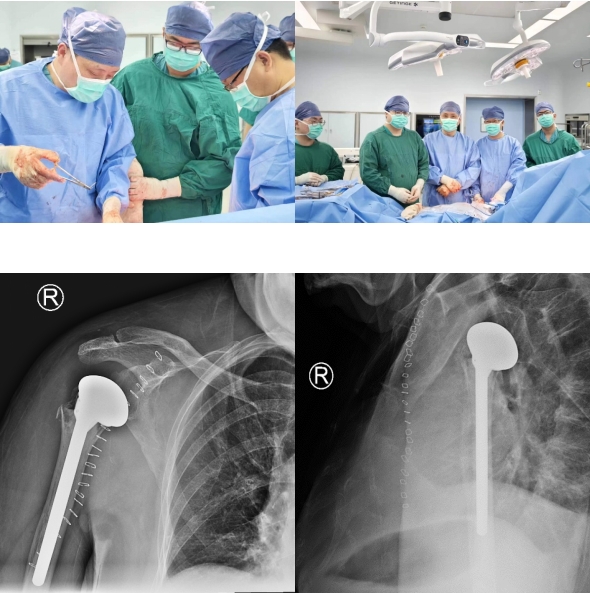

手术方案制定后,经过缜密的术前准备,手术如期进行。整个手术过程仅持续了2个小时,杨小海主任团队顺利完成了我院骨科第一台肩关节置换手术,填补了苏大附四院骨科该术式开展的空缺。术后患者复查X片提示肩关节假体位置满意,手术获得成功。在佩戴支具固定1-2周后,申阿姨便可开始患肩的功能锻炼,申阿姨及其家人对此次治疗就医经过表示满意。

术后复查X片,假体位置满意